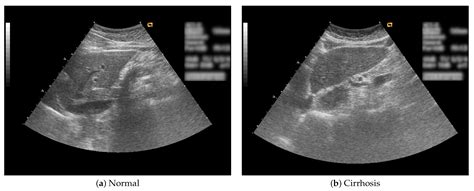

Interpreting the results of a liver ultrasound involves assessing the images for any abnormalities. A normal liver ultrasound will show:

• Size and Shape: The liver should be of normal size and shape, with smooth edges.

• Echogenicity: The liver tissue should have a uniform echogenicity, indicating a healthy structure.

• Blood Flow: Normal blood flow through the liver and its vessels.

• Absence of Abnormalities: No cysts, tumors, or other abnormalities should be present.

• Cirrhosis: Advanced liver disease characterized by scarring and loss of liver function.

• Not Suitable for All Conditions: Some liver conditions, such as early-stage cirrhosis, may not be detectable on an ultrasound.

• normal liver vs cirrhosis ultrasound